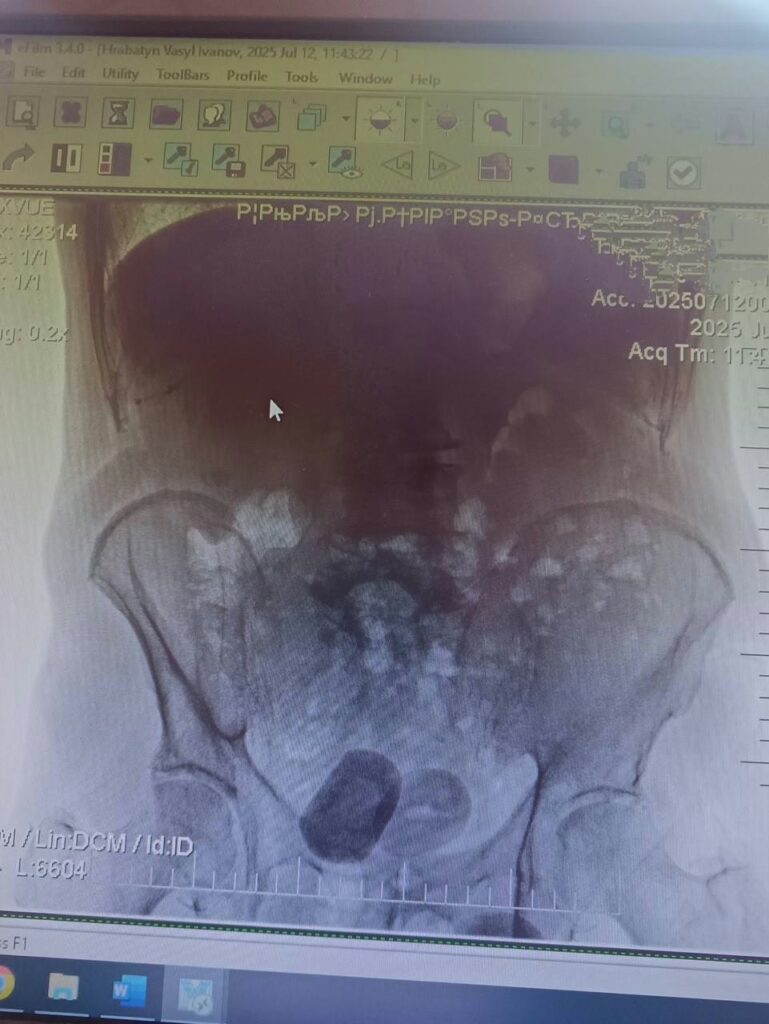

76-річний мешканець Івано-Франківська звернувся до лікарів зі скаргами на кров у сечі. Під час обстеження медики виявили у нього два камені сечового міхура, кожен з яких мав розмір 4 сантиметри.